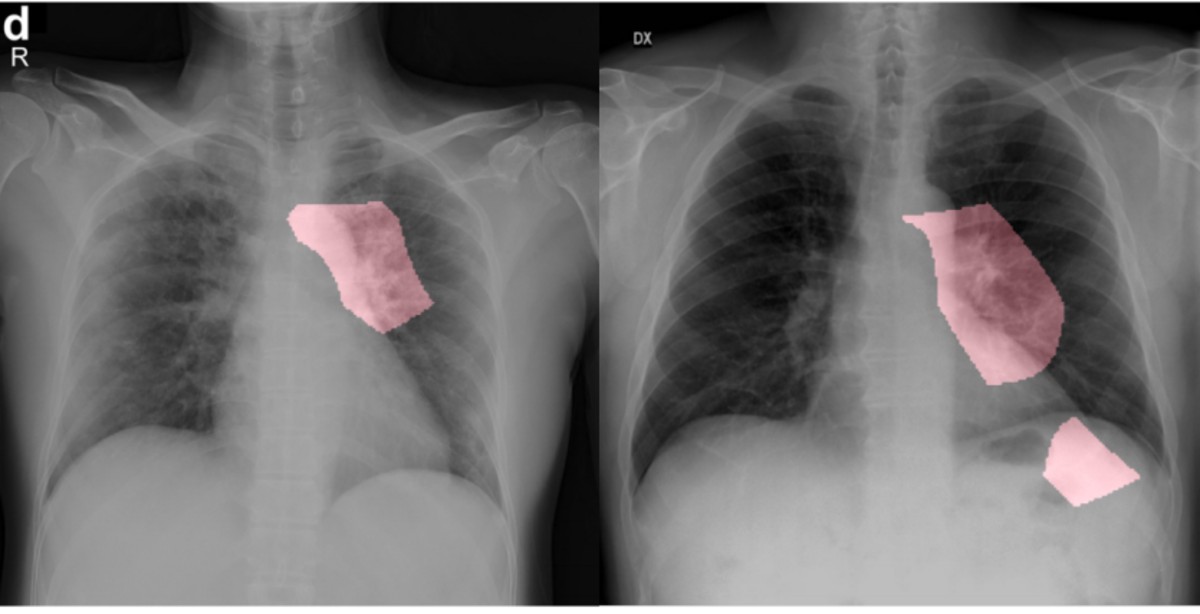

COVID-Net AI Tool Can Help in Identifying COVID-19 in Chest X-Rays

COVID-Net was trained using 5,941 chest X-rays of 2,839 patients. All of these patients had different conditions – some had bacterial infections, some had non-COVID infections, while some had COVID-19 infections.